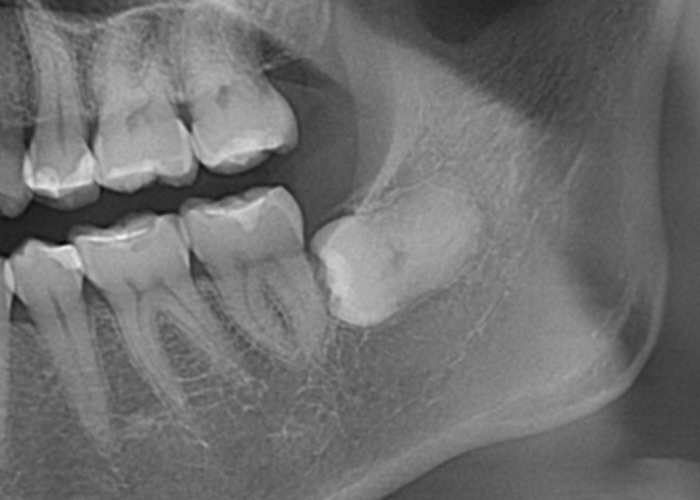

半埋伏智歯(部分的に露出している)

半埋伏とは、親知らずの一部が歯肉の下に埋まっており、一部が口腔内に露出している状態を指します。

露出している部分には、歯垢や食物がたまりやすくなり、炎症や感染、虫歯のリスクが高まる場合があります。

また、半埋伏の親知らずは、周囲の歯や歯肉に圧迫を与え、痛みや不快感を引き起こすこともあります。

さらに、半埋伏の親知らずが隣接する歯に対して圧力をかけることで、歯列の乱れや移動が起こる場合もあります。